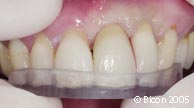

15. | 病人第二次就诊4个星期后,取下临时修复体戴入一体化基台冠前。 |

27. | 就位的一体化基台冠的右侧观。 |

28. | 就位的一体化基台冠的左侧观。 |